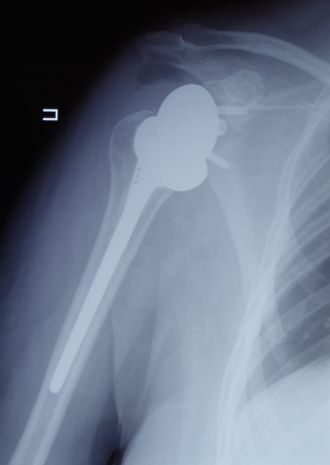

Чтобы восстановить функцию плечевого сустава, врачи травматолого-ортопедического отделения ФМБЦ им. А.И. Бурназяна ФМБА России впервые выполнили реверсивное эндопротезирование плеча. В ходе операции хирурги удалили поражённую головку плечевой кости, на место которой поместили реверсивный эндопротез – плечевой компонент протеза вогнутый, а со стороны лопатки выполнен в форме сферы. Такой тип протеза позволяет восстановить функцию сустава при дефиците мышц вращательной манжеты плеча и показывает лучшие результаты, чем другие эндопротезы.